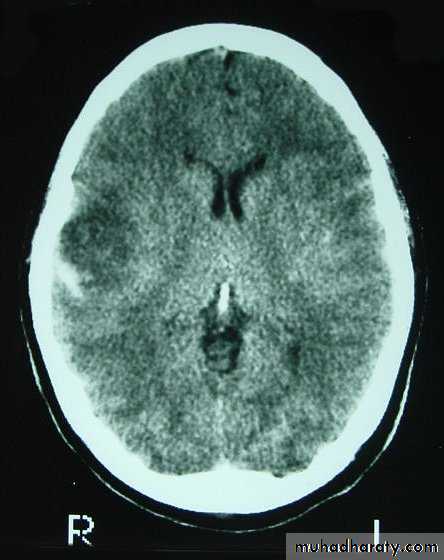

CT scans demonstrates contusions as small areas of haemorrhage in the cerebral parenchyma.

Contusions may resolve with the accompanying deficits or they may persist.

3. Cerebral Contusion

Neurosurgery